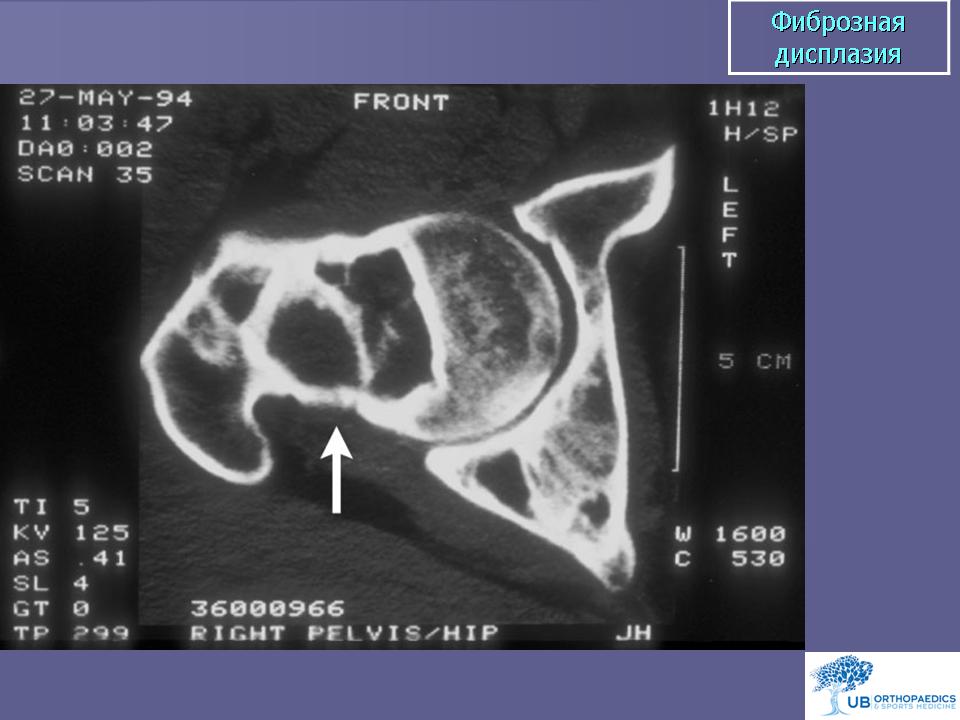

Фиброзная дисплазия. Этиология неизвестна. Заболевание наблюдается в возрасте 10-30 лет. Клинически различают монооссальную и полиоссальную фиброзную дисплазию. При некоторых формах полиоссальной дисплазии поражаются три системы - кожа (пигментация), кости и эндокринная система. Опухоль содержит низкодифференцированную доброкачественную фиброзную строму с образованием кости. Фиброзная дисплазия характеризуется медленной резорбцией костной ткани, вызывая неопределенные ноющие боли в костях, часто сочетается с патологическим переломом, причем в значительном числе случаев заболевание обнаруживается лишь после внезапно наступившего патологического перелома. При полиоссальной форме поражается несколько костей, иногда лишь на одной стороне. Заболевание необходимо дифференцировать с патологическими переломами, возникшими на фоне злокачественных опухолей костей, в частности с высокодифференцированной остеогенной саркомой (low grade). Против наличия высокодифференцированной остеогенной саркомы говорит отсутствие анаплазии и полиморфных по размерам и форме ядер в клетках фиброзной стромы. При сканировании костей могут выявляться «горячие» очаги. Рентгенологически в зонах поражения видны участки просветления («часовое стекло», «мыльные пузыри»), могут выявляться множественные патологические переломы. При сращении таких переломов проксимального конца бедренной кости в зоне поражения фиброзной дисплазией возникает симптом, называемый «пастушьим посохом (клюкой)». Пациенты с полиоссальной фиброзной дисплазией должны быть обязательно обследованы на предмет скрытых гормональных и метаболических нарушений. Малигнизация фиброзной дисплазии происходит редко (0,5%).

Фиброзная дисплазия